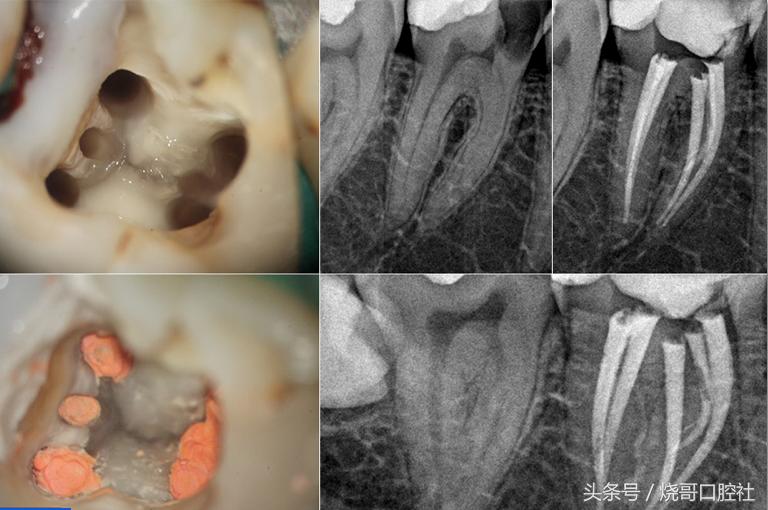

2、深龋

蛀牙过深牙本质被破坏,牙齿变黑而且还会剧痛,说明牙髓已经死去,牙体需要保护就得杀死牙神经,再用生理盐水冲洗,封药消炎几次,注意换药期间将拔髓针拔一下,检验是否有残髓,才可以做氢氧化钙和氧化梓双层垫底,再继续填充纳米树脂。